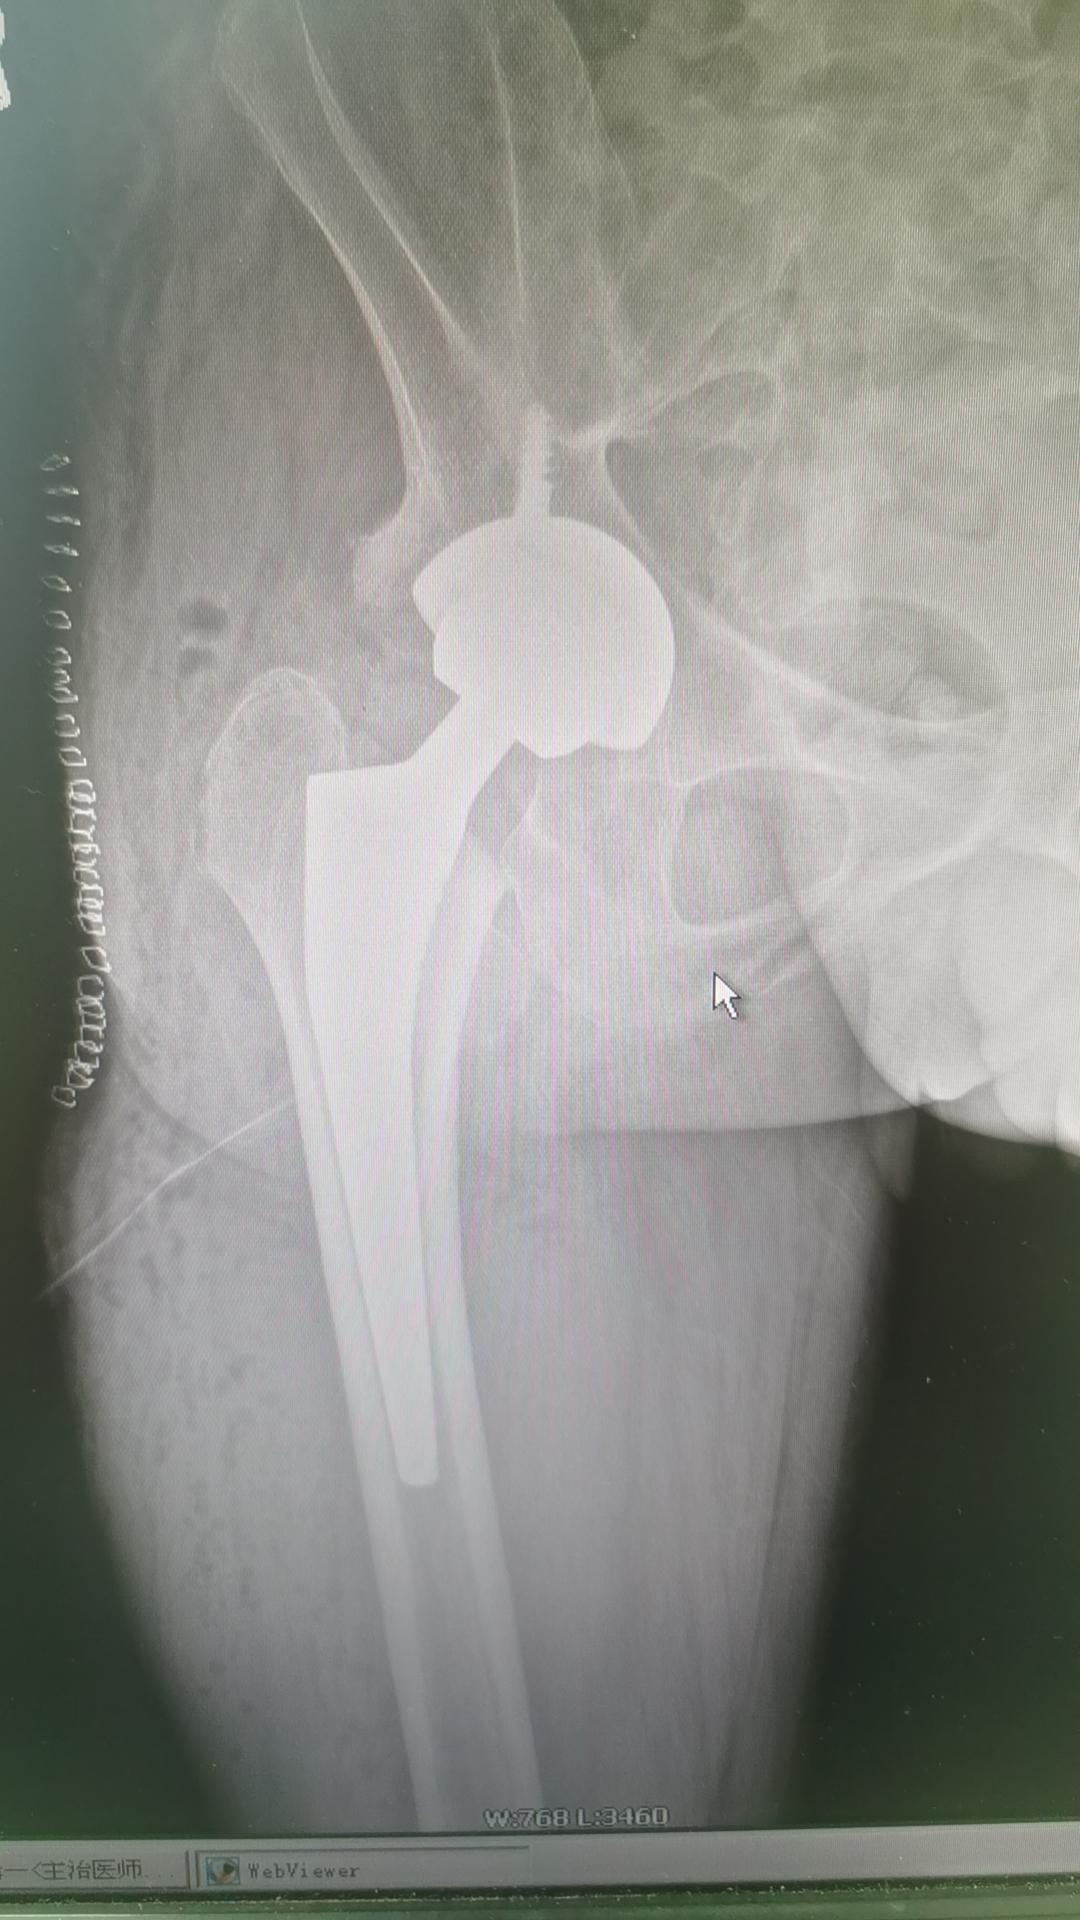

髋关节置换。融合髋,就是髋关节骨性融合,没有一点点活动度,是初次THA的难度天花板,一切顺利🌹